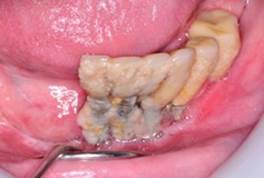

Clasificación de Peri-implantitis5

Moderada: Profundidad de sondaje >6 mm, con sangrado y/o supuración en >2 sitios del implante, y pérdida ósea entre 25% - 50% del largo del implante (Fig. 3).